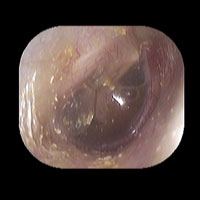

右急性中耳炎(中等症)

鼓膜がやや赤くなっています。鼓膜の奥に膿が透けて見えています。鼓膜の腫れはありません。抗生剤の内服で鼓膜切開を行わずに16日目で治りました。

14日目